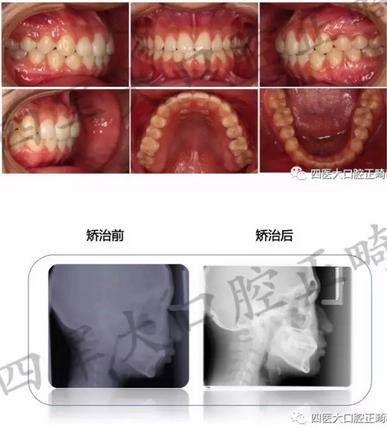

在剛剛閉幕的“絲綢之路口腔正畸學(xué)術(shù)年會(huì)暨疑難錯(cuò)合畸形多學(xué)科綜合診治研討會(huì)”上,我們隆重舉辦了一年一度的四醫(yī)大口腔正畸科青年醫(yī)師病例展示,各路新俊都大顯身手。小編會(huì)分五輯為您呈現(xiàn)每位青年醫(yī)生的精彩病例片段,歡迎各位患者及同行朋友圍觀

來(lái)源:四醫(yī)大口腔正畸科